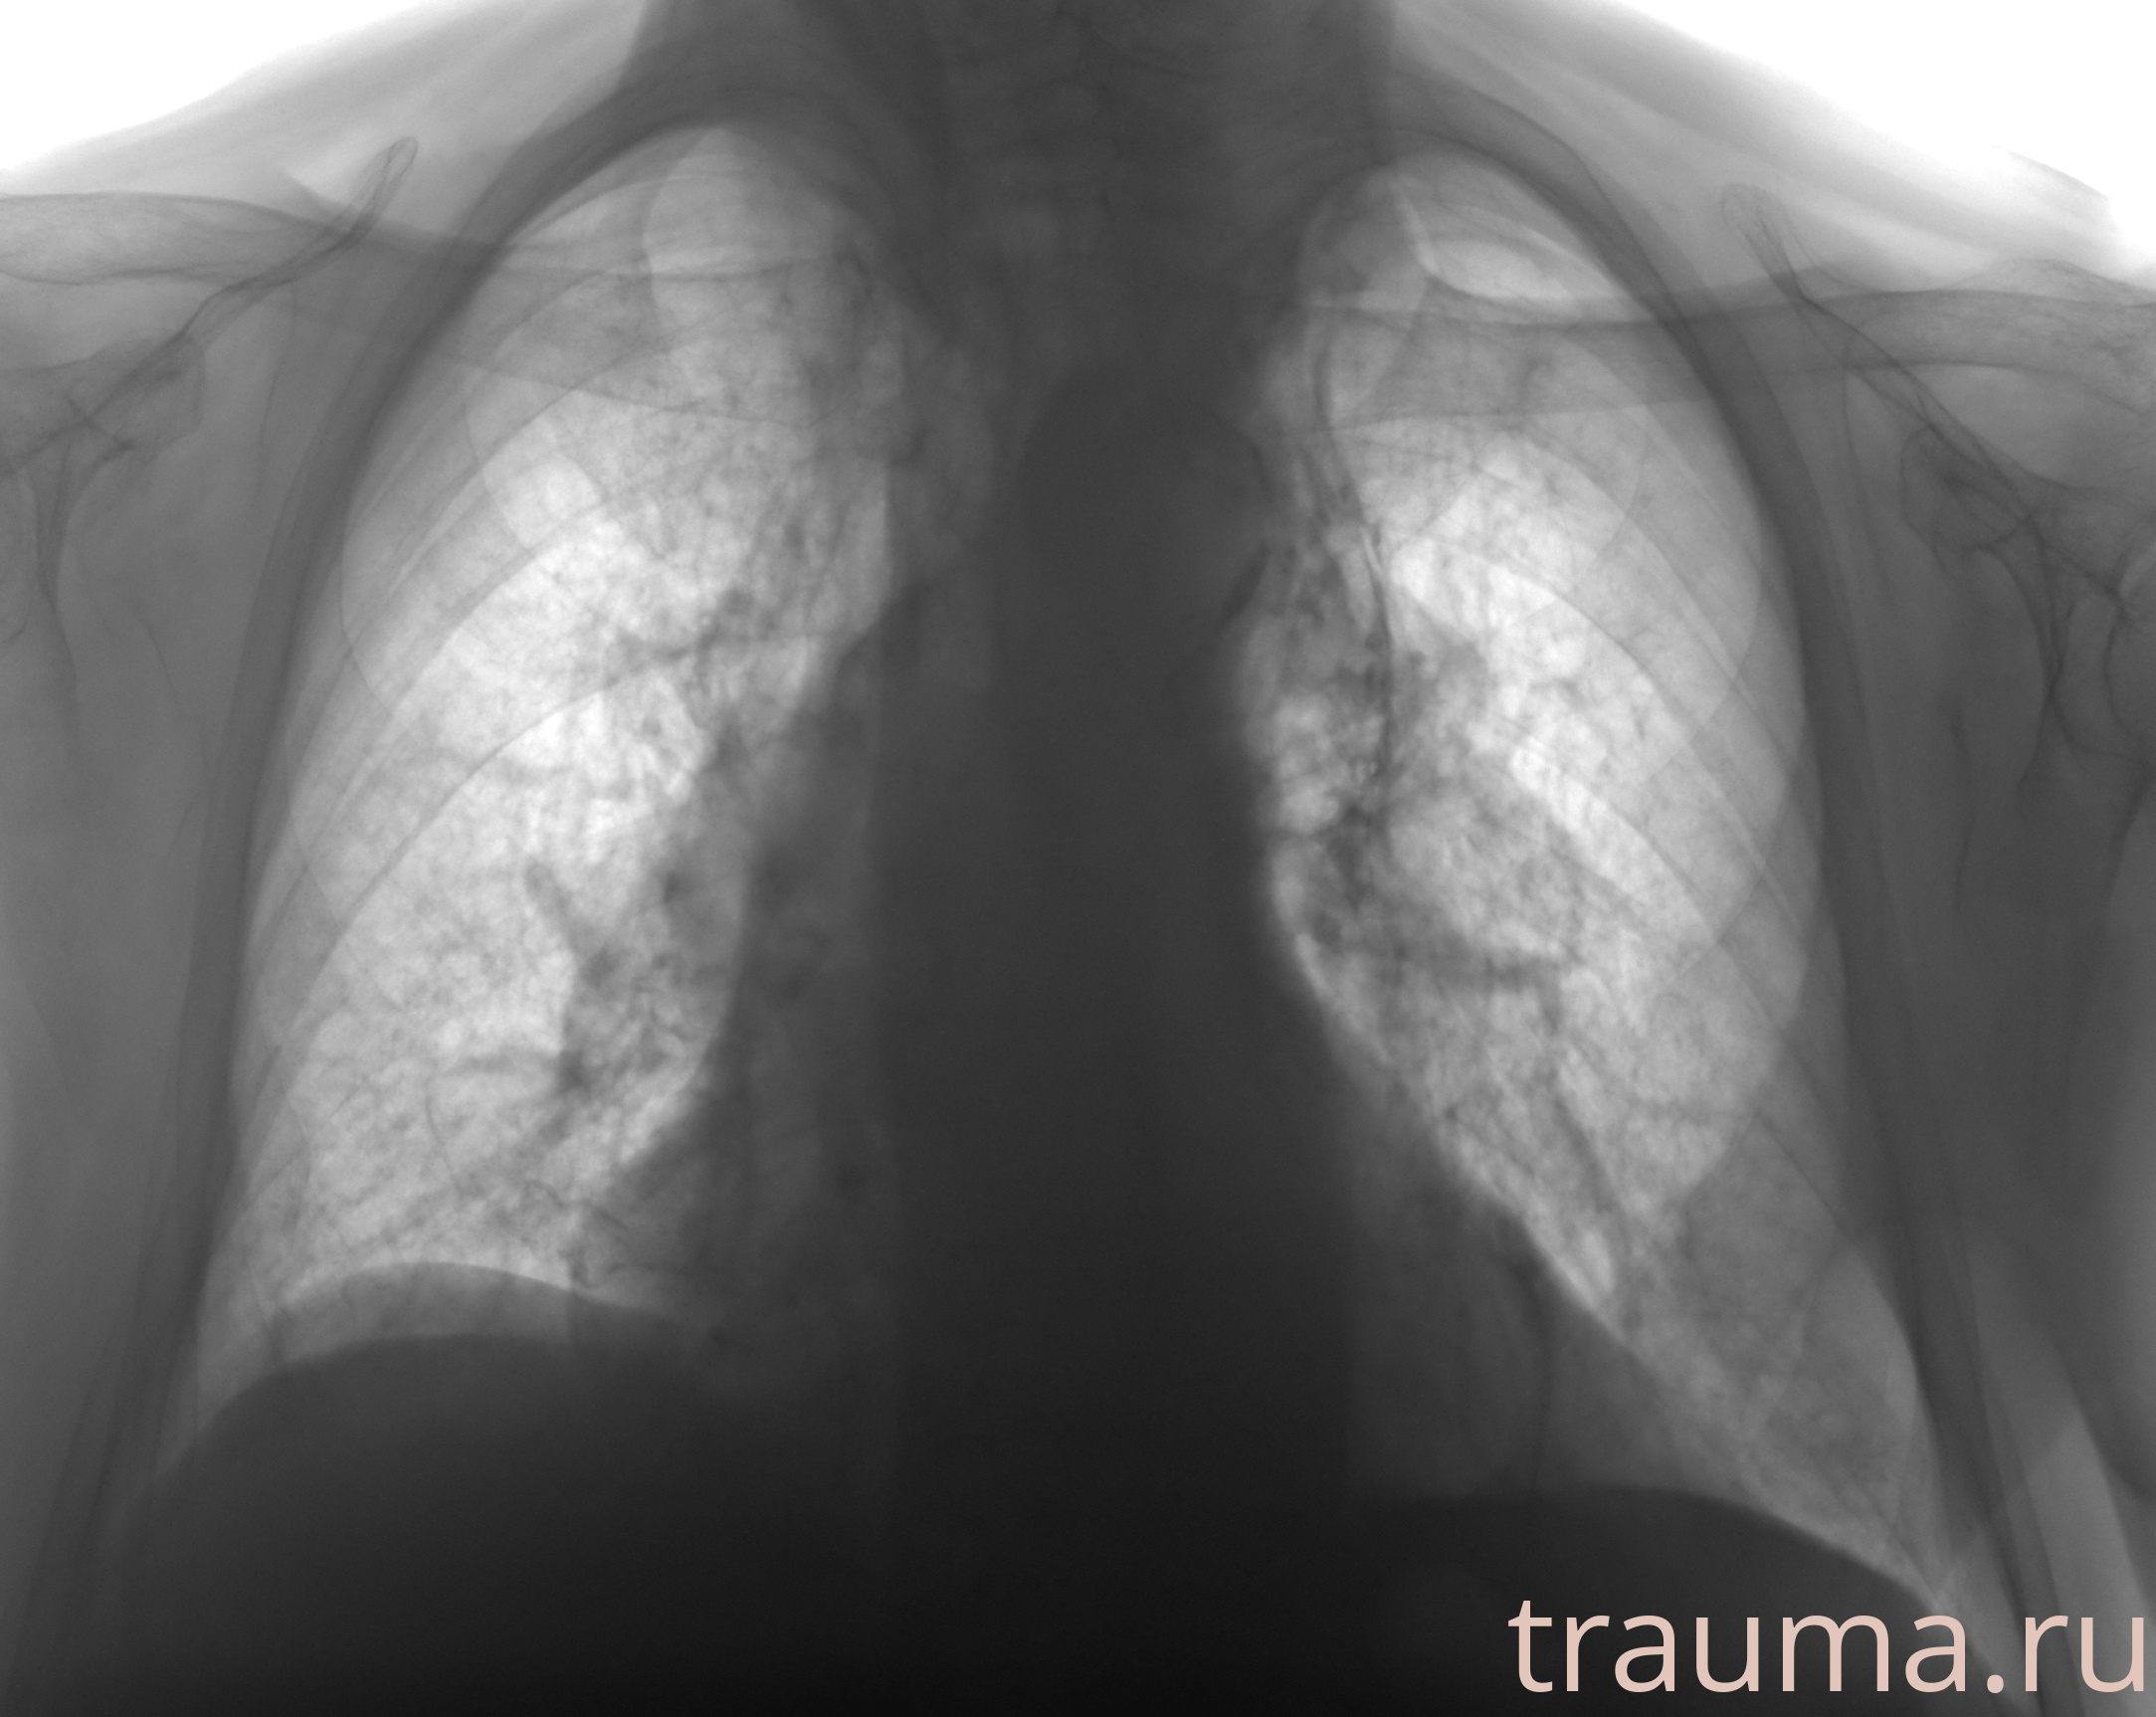

Рентген на дому: по вашему адресу приезжает врач-рентгенолог, травматолог-ортопед с мобильным рентгеновским аппаратом, проводит диагностику травмы или заболевания, делает необходимые рентгенограммы, дает рекомендации по дальнейшему лечению. Получить качественные снимки в домашних условиях возможно благодаря уникальной методике, разработанной МосРентген Центром для института  Склифосовского

при переломе шейки бедра и пневмонии от компании МосРентген Центр - партнера Института имени Склифосовского